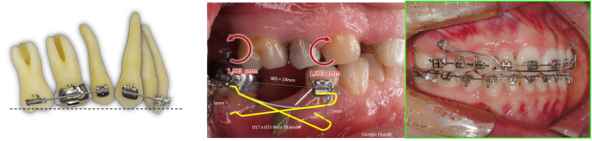

In some cases, orthodontic treatments don't follow the expected outcomes due to individual biological variations, despite precise treatment planning and meticulous design of the appliance. These complications can't always be resolved through technical skills alone; a deeper understanding of fundamental biomechanical principles of tooth movement is required. Particularly on Day 2, the focus will be on achieving root movement, which is challenging with aligners. Participants will learn the fundamental principles behind root movement and practice these techniques to better apply biomechanics in clinical settings.

The mechanics of root movement (1) |

The mechanics of root movement (2) |